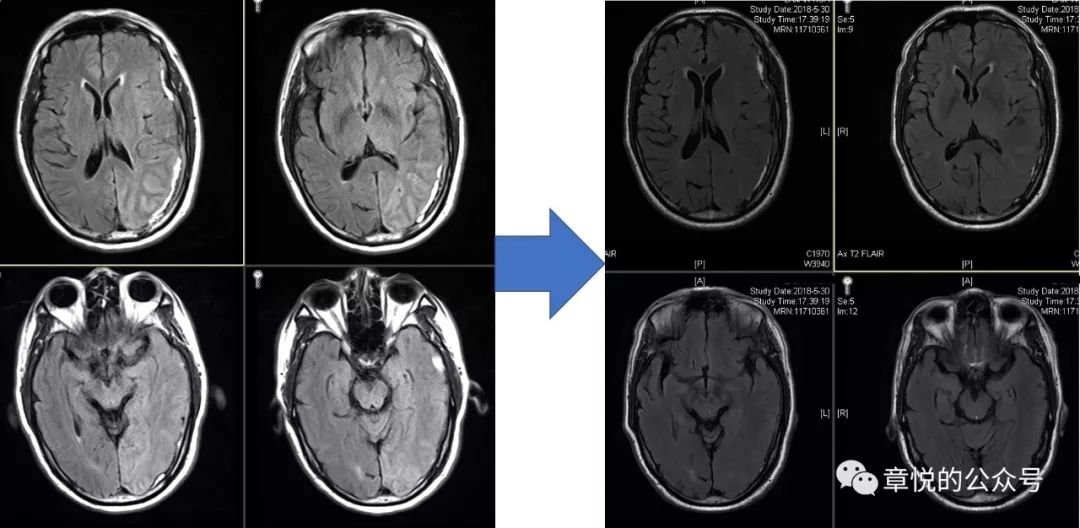

患者入院后,我们发现他的血糖十分高,空腹血糖11 mmol/L,餐后高达18 mmol/L,糖化血红蛋白超过11%,起初家属对我们提出的胰岛素治疗有点感冒,但连续3天患者情况不好于是就听从我们的意见,晚上一针下去,第二天早上血糖降到7 mmol/L,患者意识障碍明显好转,并且能够连词成句了,家属对此十万分的满意,毕竟是华山医院,一针见效!此后的几天,病人空腹血糖基本就控制6-7 mmol/L,餐后血糖8-9 mmol/L,病人情况一天好过一天,到第5天,家属感觉病人情况已经好了8-9成,查体患者对答切题,言语流利,计算力正常,虽然有时候找词有点困难,但已经不妨碍他正常表达了,接着DSA检查排除了血管畸形,复查头颅磁共振发现脑叶肿胀和异常信号消失。当出院时询问患者入院时的情况,他丝毫没有印象(图9)

图9 经过降糖治疗,脑叶肿胀和异常信号消失